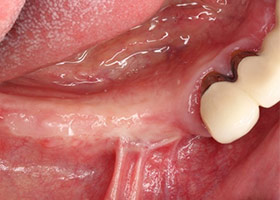

2.病患右下排,治療前狀況。

3.照片顯示此區域牙周破壞嚴重。